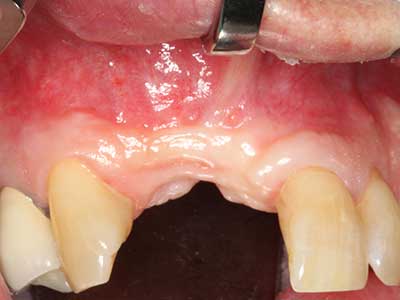

Пиезохирургията има допълнителни предимства при събиране на костни блокове. В допълнение към високата прецизност при остеотомията, описана по-горе, употребата на фините режещи накрайници значително намаляват загубата на материал. Голяма загуба на материал по време на събиране може да се очаква с дебелите накрайници, особено при употреба на борери Линдеман (Lakshmiganthan, Gokulanathan et al. 2012). Базалното разделяне, което е необходимо, особено за присадка на блок при ретромолар, е улеснено от специално създадени правоъгълни триони. В резултат на това, пиезохирургията е разглеждана като прецизна, улеснена и безопасна процедура за събиране на костни блокове в ретромоларното пространство (Happe 2007) (Фиг. 1-12).